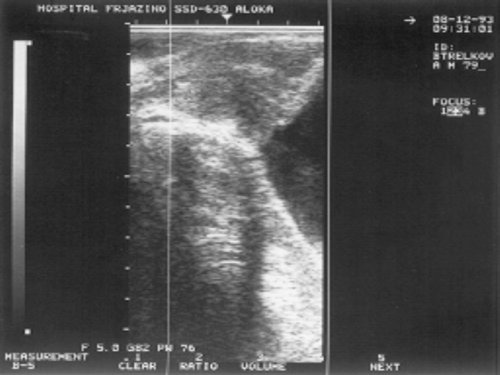

Больной Л., 62 г., поступил в урологическое отделение с распирающими болями в правом боку и пояснице, тотальной макрогематурией и aнемией. При УЗИ почек справа отмечается пиелокаликоэктазия с неоднородным повышенной эхогенности содержимым лоханки (рис. 1), камней и патологических изменений со стороны паренхиматозной структуры почек не выявлено.

Рис. 1. УЗИ почки - пиелокаликоэктазия с неоднородным, повышенной эхогенности содержимым лоханки.